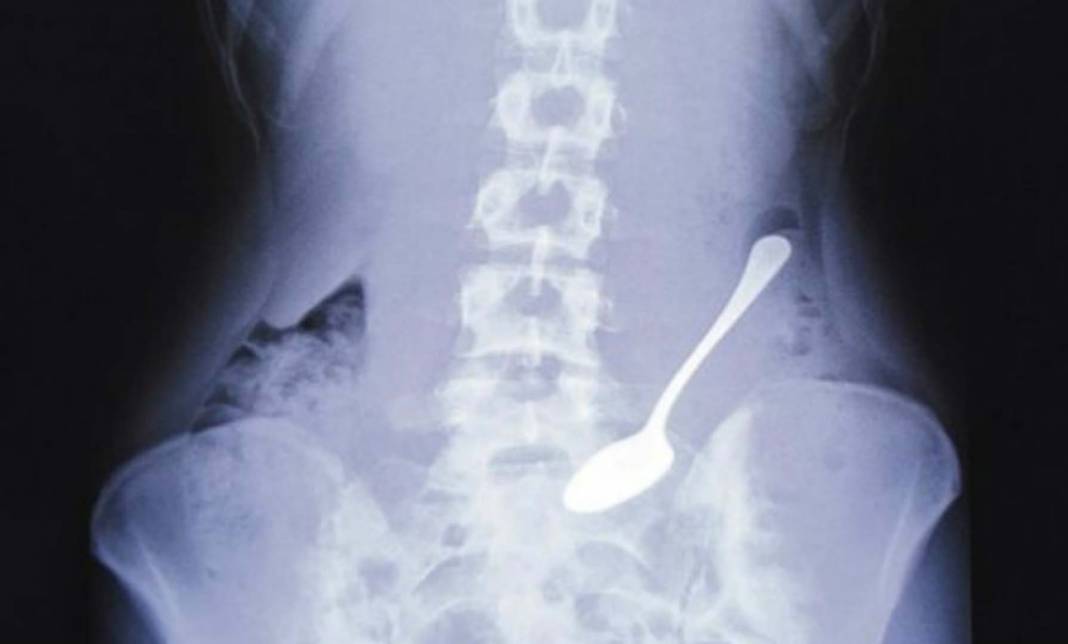

Hindistan'ın Muzaffarnagar bölgesinde yaşayan bir adam, inanılmaz derecede şiddetli karın ağrıları çektiği için hastaneye başvurdu.

Doktorlar ağrının nedenini tespit etmek için adamı röntgen ve tomografi taramasına soktu.

Tümör olabileceğinden şüphe eden uzmanlar, tarama sonuçlarında adamın midesinde çok fazla yabancı maddeye rastladılar.

Acilen ameliyata alınan adamın midesinden, 2 saat süren operasyon sonrası 63 metal kaşık sapı çıkarıldı.

Ameliyatı gerçekleştiren doktor vaka ile alakalı, "Ameliyatta yabancı cisimlerin çelik kaşık olduğunu fark ettik. Bu kadar çok kaşık çıkınca şok olduk. Tam 63 tane vardı. 35 yıllık meslek hayatımda gördüğüm nadir tıbbi vakalardan biriydi" şeklinde konuştu.

Adamın kaşıkların başını kırıp saplarını yuttuğu tespit edildi.

Midesinden onlarca metal sap çıkarılan adam, yaklaşık 6 aydır bunu yaptığını söyledi.